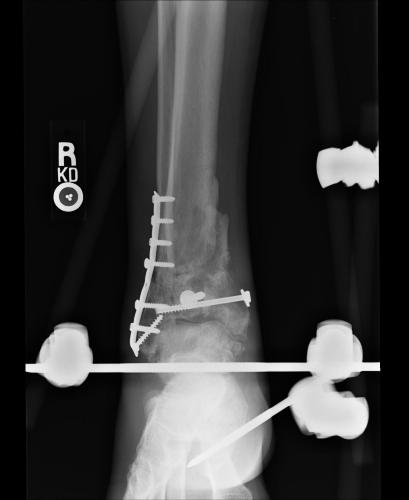

Postoperative (13th) images of left ankle

The image(s) displayed here were created following Liam's 13th surgery which was performed by Dr. Saunders. After a few hiccups getting

the surgery scheduled, Liam spent most of the September 13th afternoon in his 13th surgery. ;-) The surgery lasted about 5 hours and according

to the doctor, it was a good surgery. The 1st photo shows the new frame bracing that holds Liam's ankle together. The next series of photos show

various angles of the ankle and the rods that go from the frame into and through the left ankle. There was some concern that the swelling would

burst and allow for infection. Looks like we are now past that concern. Liam is still on antibiotics to ward of potential infection. The flesh

images show how the skin reacts to having the leg adjusted by the brace. The doctor has had to cut the skin to allow the rods to move freely.